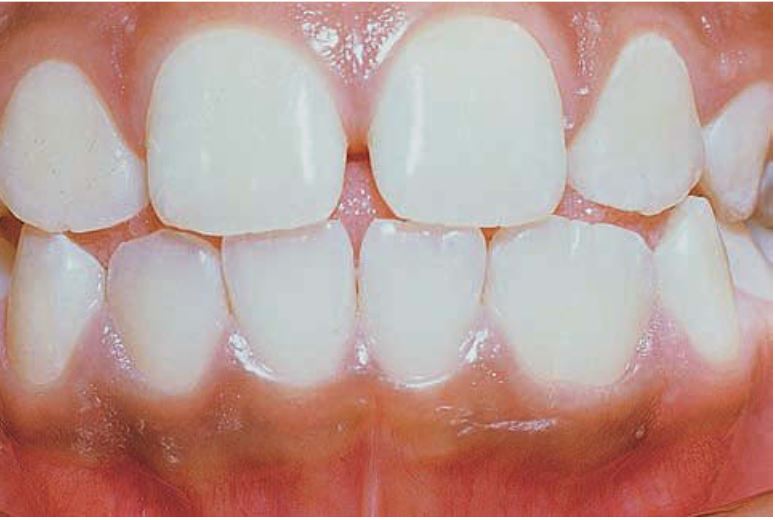

Răng sinh đôi (gemination)

Xảy ra khi một mầm răng có khuynh hướng chia thành 2 răng, nhưng sự phân chia này không hoàn toàn.

Tỉ lệ gặp ở răng sữa cao gấp 5 lần so với răng vĩnh viễn. Răng hay gặp nhất là răng cửa sữa hàm dưới và răng cửa vĩnh viễn hàm trên, bị một bên nhiều hơn hai bên.

Răng sinh đôi cũng hay có rãnh dọc theo mặt ngoài hoặc mặt trong, khía ở rìa cắn. Trên lâm sàng rất khó chẩn đoán phân biệt giữa răng dung hợp với răng sinh đôi.

Trên phim thì thấy răng sinh đôi chỉ có một buồng tủy rất rộng, chân răng to, thân răng chẻ đôi. Tuy vậy vẫn còn nhiều biến thể khác.